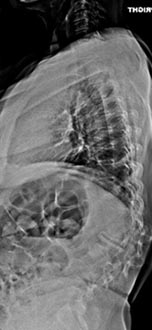

59 year old woman with Scholiosis with severe back pain.

1 year postop from surgery and pain free.